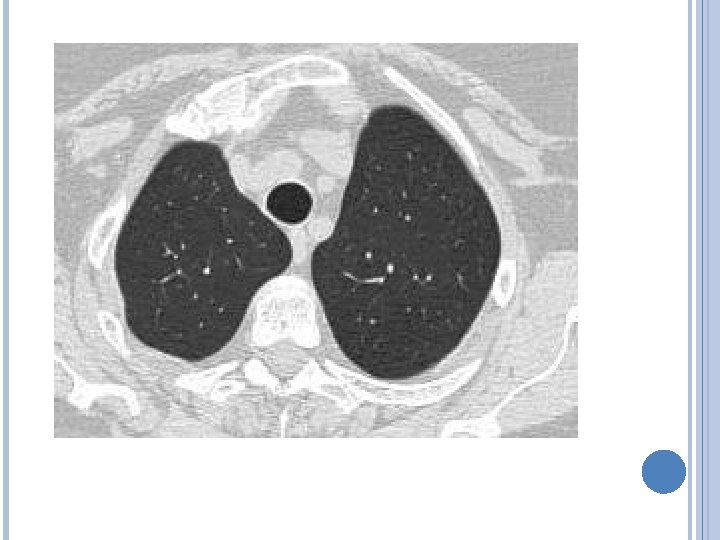

IMAGENES